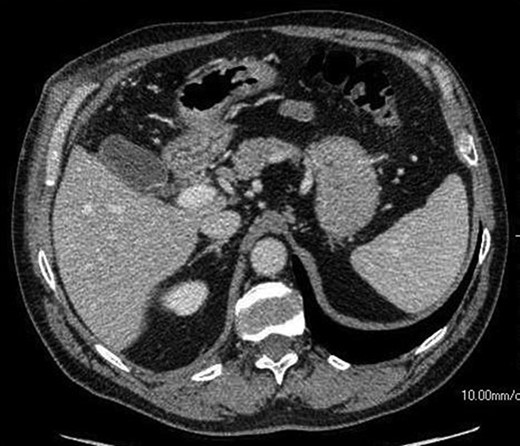

The patient presented to the hospital 4 months after the initial operation with right upper quadrant pain. CT abdomen established the appearance of a normal gallbladder despite his history of subtotal cholecystectomy (Fig. 2). He underwent an elective laparoscopic cholecystectomy 1 month later, which revealed an apparently complete gallbladder that was extensively walled off by omentum. An intraoperative image is shown in Fig. 3.

An axial CT image shows collection in the gall bladder fossa closely resembling a normal gallbladder appearance.

This study presents radiological correlation of an interesting surgical case. The progressive ultrasound images demonstrate organization and localization of a postoperative collection, which is later indistinguishable from normal biliary anatomy on CT. This finding is confirmed intraoperatively.